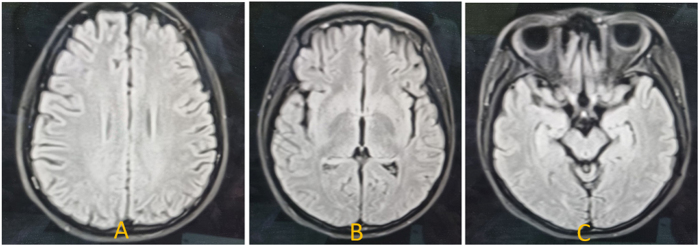

Case presentation: A 16-years-old female presented with long history of generalized weakness since age of 10 years, followed by bilateral sensorineural hearing loss, bulbar symptoms, and limb spasticity. Neurological examination revealed upper motor neuron signs in upper limbs, lower motor neuron signs in lower limbs, and bulbar involvement. Nerve conduction test was normal however, MRI showed early degenerative changes, and diagnosed with J-ALS after careful evaluation. She was started on Riluzole. Despite ICU care and supportive interventions including PEG and tracheostomy, she succumbed to respiratory failure.